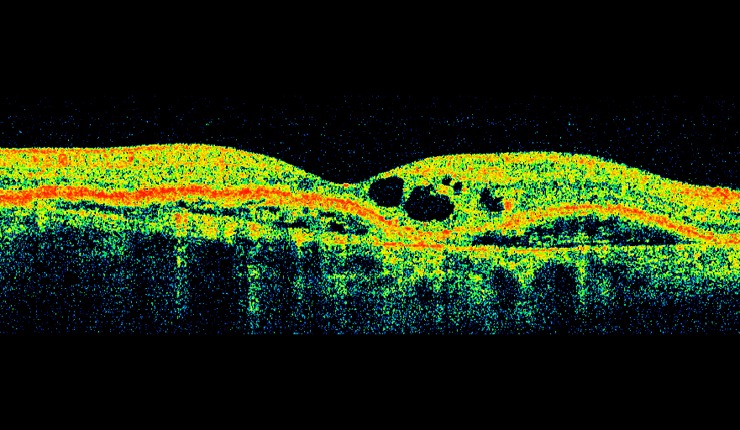

3D OCT of retinal angiomatous proliferation (RAP) showing news vessels tracking through the retina and associated intra-retinal oedema.